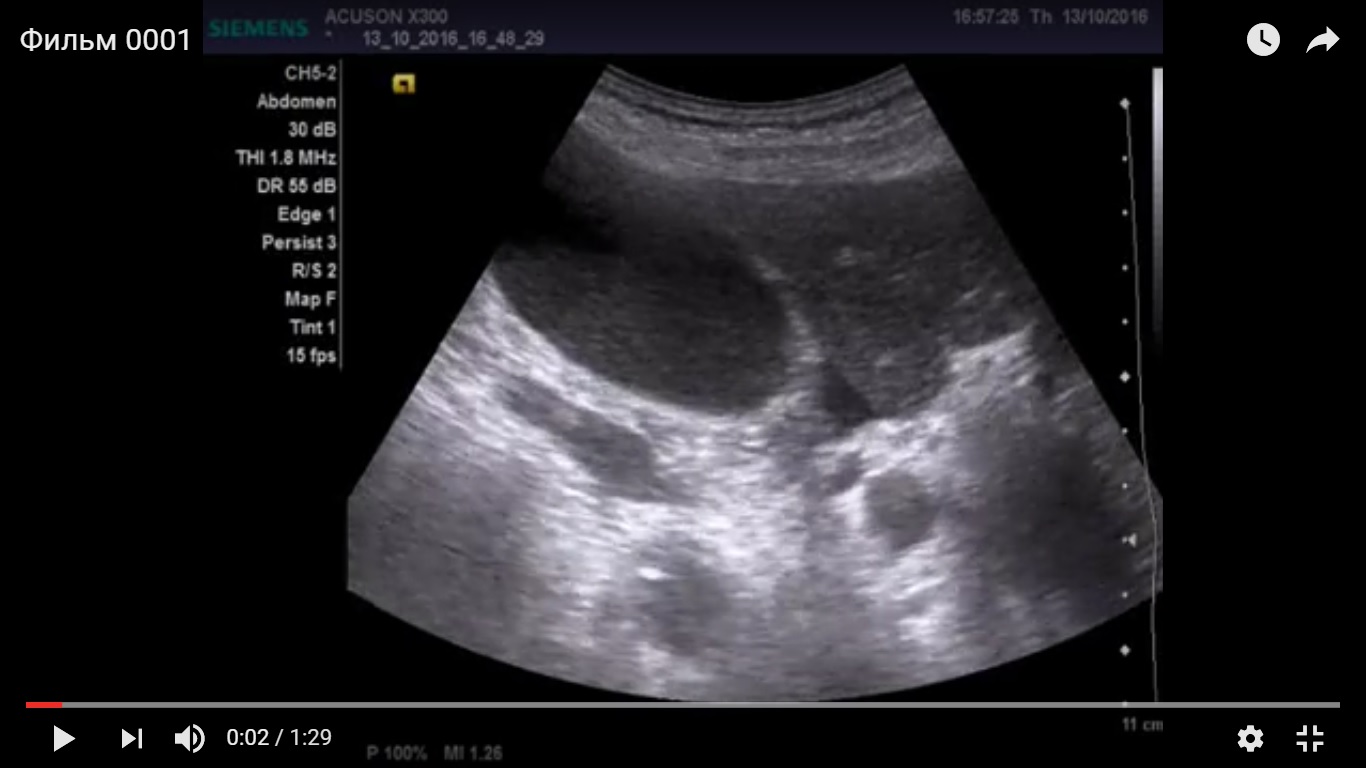

Дедушка лет 80, поступил по скорой с жалобами на боли в животе, провели узи, увидели выраженный асцит. Затем кто то видимо подсобрал анамнез, поставил катетер в мочевой и вывел 4 литра мочи. Для того что бы исключить хир. патологию и отправить дедушку на излечение в урологию повторно проведено уз исследование.

желчный пузырь увеличен 11*5 см, заполнен крупнодисперсной взвесью, в области шейки свободная жидкость. Дискинезия ЖВП?

есть признаки да. учитывая гемодинамически значимый стеноз ВБА, я бы склонился к эмпиеме пузыря, на фоне атеросклеротических изменений пузырной артерии. Учитывая возраст, клиника может быть стёрта, а учитывая наличие свободной жидкости, можно подумать о вялотекущей ишемии стенки и нарастающей деструкции. Я так бы рассудил.

Ишемический некроз стенки желчного пузыря теоретически может быть и он очень плохо диагностируется при УЗИ.

Но должны быть другие признаки воспаления, например, околопузырный инфильтрат и хоть какое-нибудь изменение стенок.

то что есть выложил. Хирурги сказали что клиники нет, перевели в урологию, но опыт показывает , что не всегда они правы. Считаю , что на узи не нормальная картина.